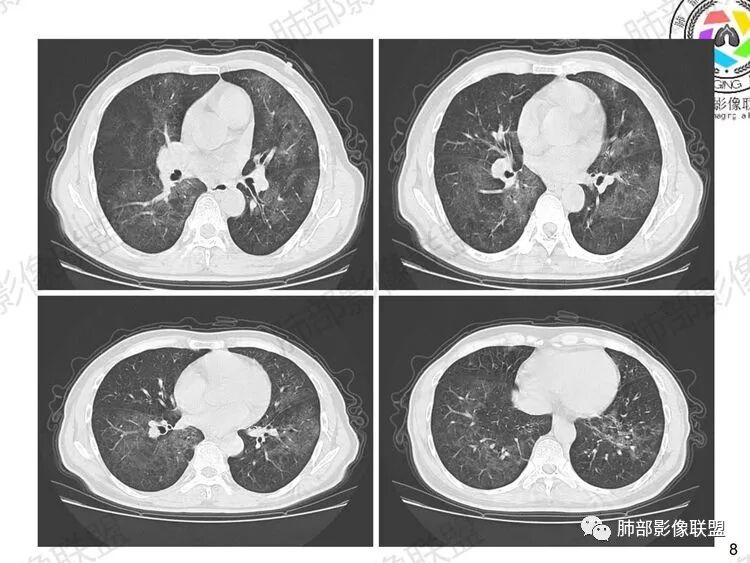

早期:孢子菌滋养体吸入附在肺泡壁上,破坏I型肺泡上皮细胞的细胞膜,使细胞坏死及毛细血管通透性增加。液体渗出到肺泡腔内,病灶主要位于肺泡内,肺泡腔密度增高,间质这时受累相对轻,因此早期为渗出期,病变由中心向外周分布,表现为两肺多发对称性的弥漫斑点状、粟粒状阴影,边界清楚。

中期:孢子菌在肺泡腔内大量繁殖,引起炎性渗出及肺泡上皮增生,肺泡液内含有滋养体的嗜酸性渗出物及纤维蛋白和脱落的上皮细胞,Ⅱ型肺泡上皮细胞增殖修复受损的肺泡毛细血管间膜,肺间质内巨噬细胞、浆细胞和淋巴细胞增殖导致间质性肺炎,就是说有肺泡腔的密度增高,也有间质的增厚,整个肺受累区域密度都增高,形成以肺门为中心双侧对称的弥漫性磨玻璃样改变,胸膜下较少累及,呈典型的月弓征,采用积极的对症治疗后,大多数病变可吸收消失。

注意肺孢子菌肺炎的肺部影像看上去比较“干”,不会呈现重力趋势。肺血管影及支气管影都比较清楚,尤其是含气支气管影,常常会衬托得格外清晰。

影像表现:

1、双肺从中心向外周对称性弥漫分布的磨玻璃密度影,无重力分布特点

2、中内带分布为主,胸膜下较少受累,可见月弓征

3、下肺纤维灶形成

结合患者症状典型的呼吸困难症状及影像学改变,临床症状轻,影像重,双肺从中心向外周对称性弥漫分布的磨玻璃影,无重力分布,胸膜下受累不明显(月弓征),呈典型的间质性改变,需要考虑肺孢子菌肺炎的可能,临床上需要结合有无HIV、使用免疫抑制剂病史、器官移植等免疫缺陷病史,还可以借助化验CD4细胞、LDH等进一步判断病情。